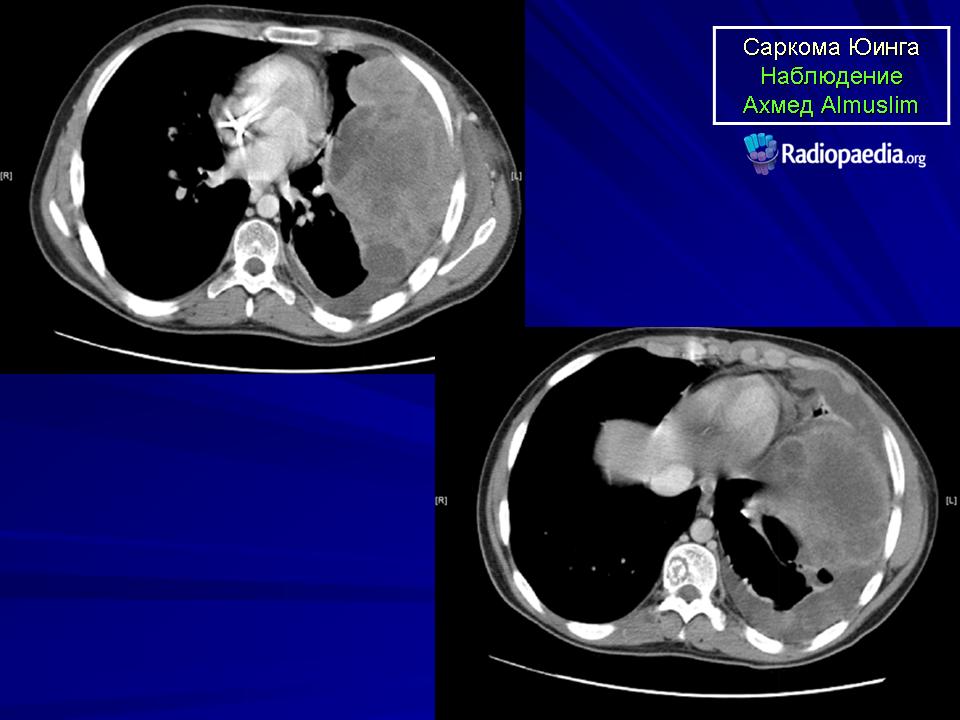

С Радиопедии.

Саркома Юинга грудной стенки.